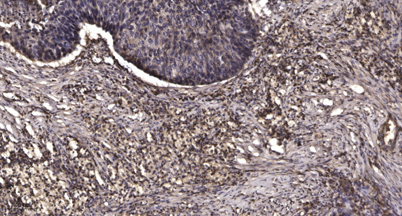

Product name: MRP-S25 rabbit pAb

Dilutions: WB 1:500-2000;IHC-p 1:50-300; ELISA 2000-20000